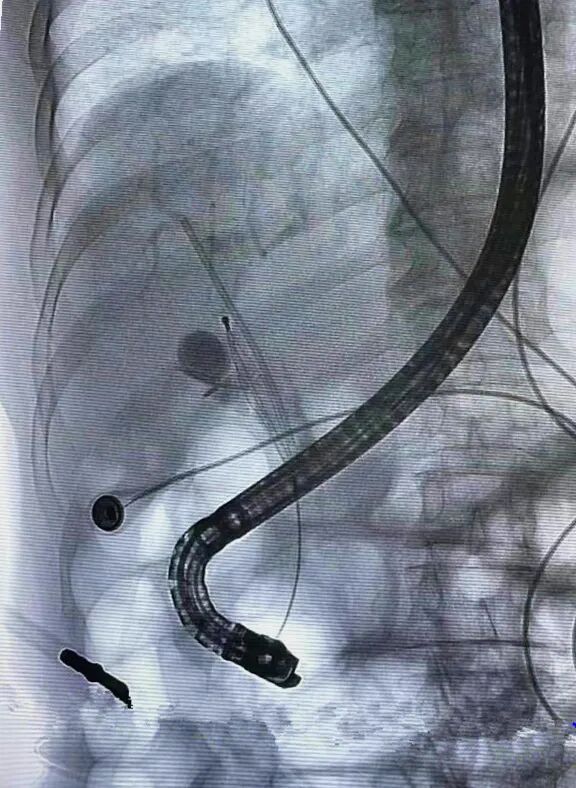

▲注入造影剂DSA透视,取石网篮置入胆管

为了最大程度减少患者创伤,医生建议患者首选ERCP取胆管支架(十二指肠镜下),如不成功,不排除腹腔镜下取支架可能。为了减少手术不适,选择无痛内镜下取胆管支架,得到了麻醉科的大力支持。普外二科副主任张勇教授带领ERCP治疗组顺利完成手术,凭借过硬技术帮助患者顺利取出放置了20年的胆道支架,以及大量泥沙样结石!